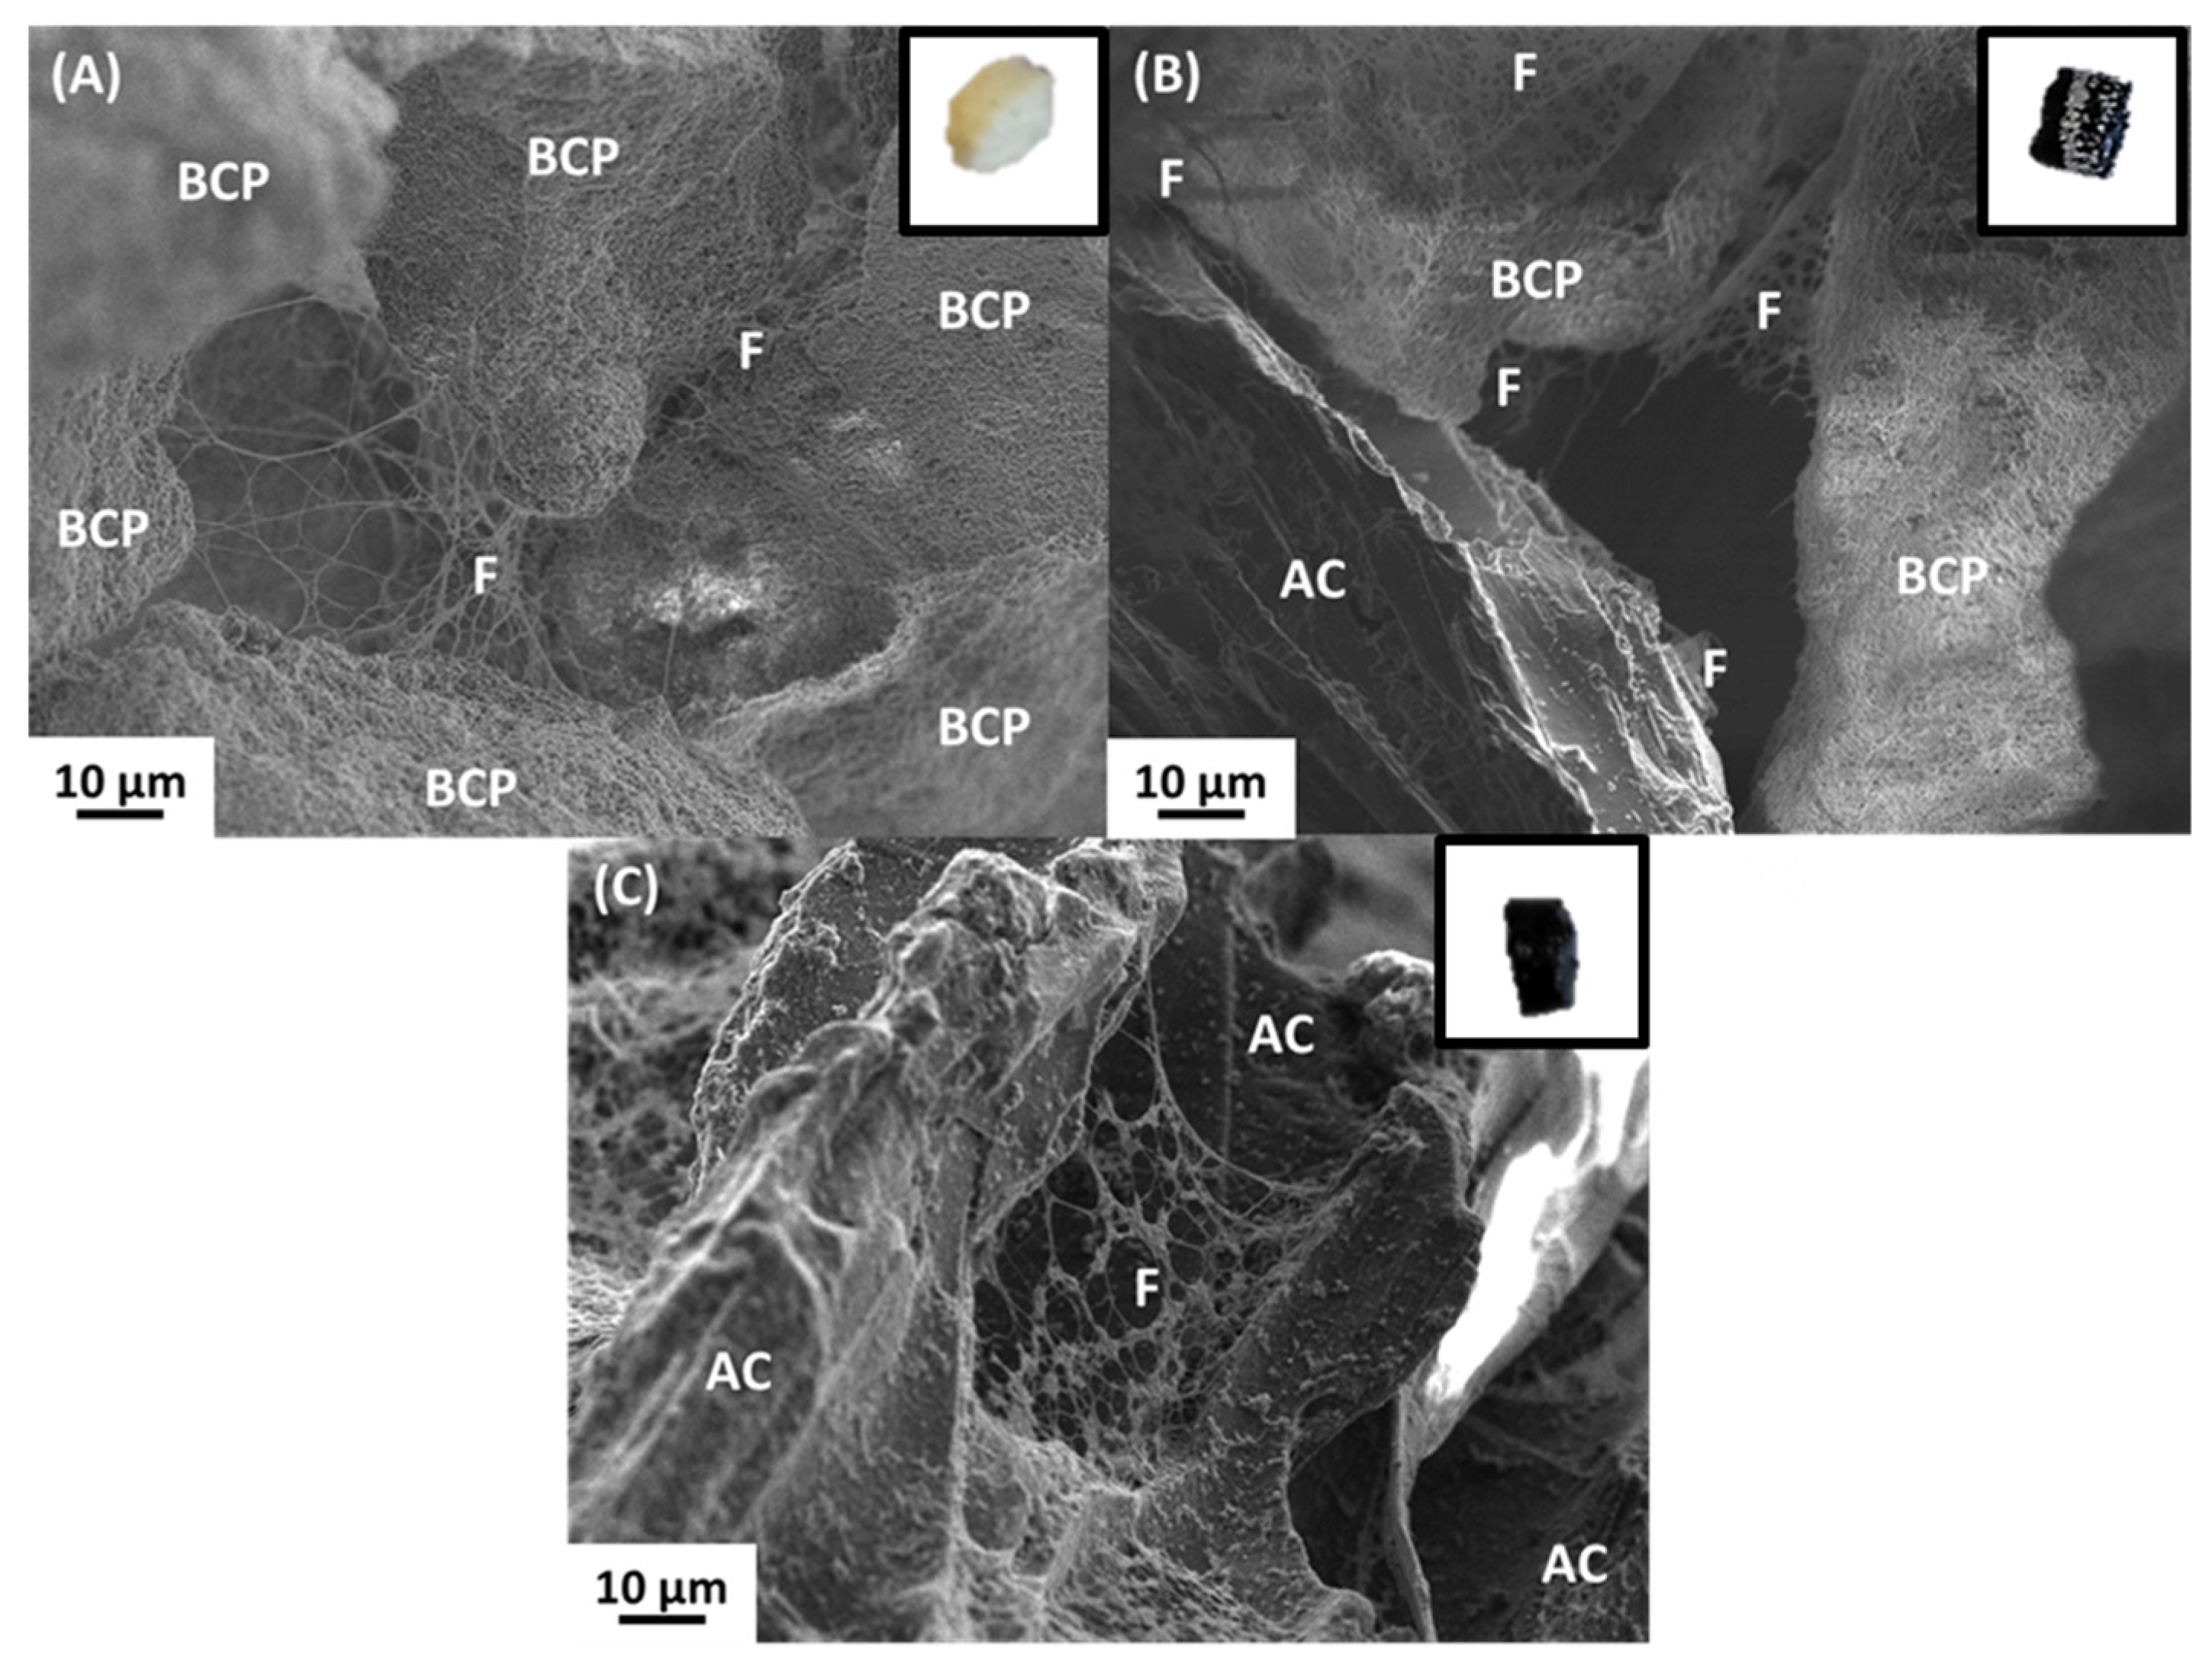

3.1. Comparison of Subcutaneous IMMATURE Bone Formation Induced by BCP, BCP/AC and AC Composites